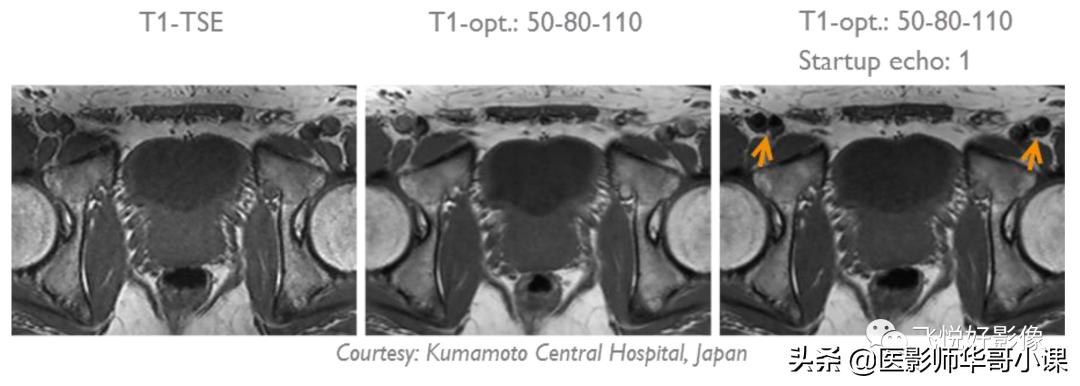

- 对于T1加权图像,使用"T1-optimized"选项:a. 只适用于2D, MS和M2D;b. 如果有截断伪影,可以尝试加一个startup echo;c. "min. angle"和"max. angle"之差太大(~40°)可能导致图像模糊;d. 减小"min. angle"可以提高T1权重,同时可以减少运动伪影;e. 增大"max. angle"可以提高SNR,但是同时也会增大SAR。

图11.PSS在盆腔中的应用,使用PSS图像锐利度提高,血流信号被抑制。